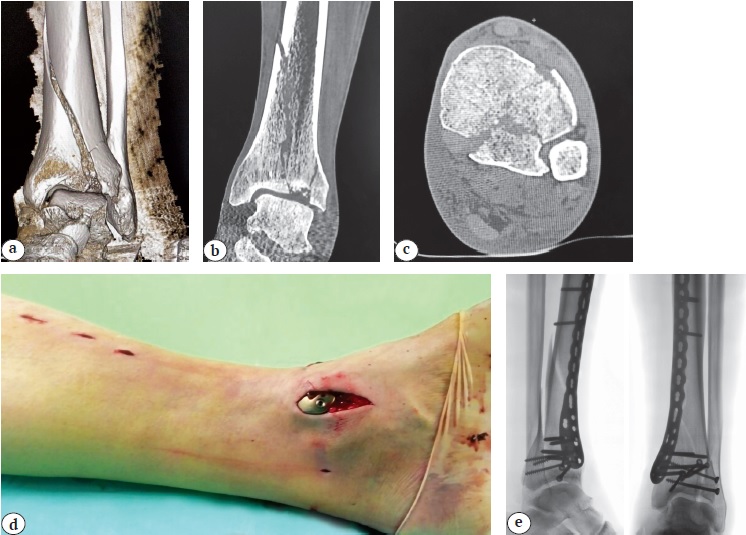

При околосуставном переломе дистального метаэпифиза ББК (тип 43А) из положения на спине выполняли малоинвазивный остеосинтез пластиной по медиальной и/или переднелатеральной поверхности ББК [3, 11, 13]. Установку выбранной в ходе предоперационного планирования пластины осуществляли из двух мини-доступов (дистального и проксимального), формируя канал под кожей и мышцами голени. Имплантат проводили эпипериостально по медиальной или переднелатеральной поверхности. Пластины анатомичной формы старались при этом позиционировать по контурам кости так, чтобы она лучше прилегала к восстановленной по оси, длине и ротации ББК, а винты, вводимые в дистальный отдел пластины, проходили субхондрально, не перфорируя при этом суставную поверхность (рис. 1).

Рис. 1. Перелом пилона типа 43С1 у пациента 68 лет: a, b, c — данные первичной СКТ, позволяющие оценить расположение основных костных фрагментов; d — хирургические мини-доступы; e — рентгенологический результат операции

Figure 1. Type 43C1 pilon fracture in a 68-year-old patient: a, b, c — initial CT scans showing the localization of the primary bone fragments; d — medial mini-incisions; e — postoperative X-rays